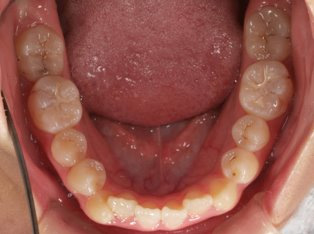

治療前

治療終了前